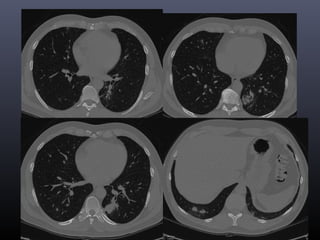

Tc torax 28-06-2011

• CONCLUSION TOMOGRAFICA:

• Nódulo pulmonar cavitado en el segmento 4 izquierdo con

afección de parénquima adyacente, lo cual como primera

posibilidad corresponde a Tuberculosis y diagnostico

diferencial de Coccidiodiomicosis.